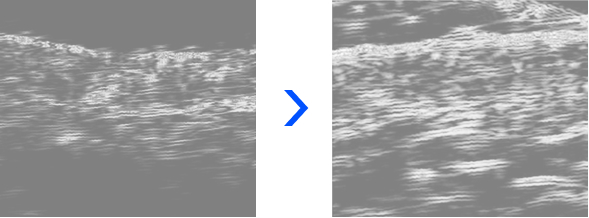

超声检测显示

治疗部位的皮肤细胞密度与结构变化

数据显示, 随着时间推移, 皮肤密度与厚度呈现渐进性增长, 胶原密度及真皮结构显著强化, 皮肤弹性获得整体提升